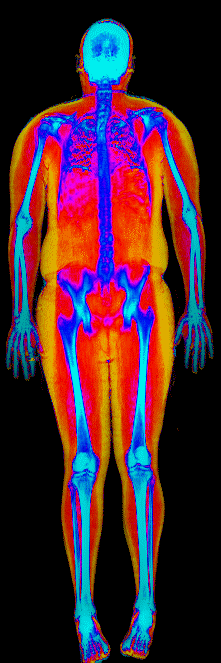

This page features real, anonymized DEXA scan images from BodyStats clients, organized by gender and body fat percentage in 5% increments. DEXA (Dual-Energy X-ray Absorptiometry) is the clinical gold standard for measuring body composition — far more accurate than scales, calipers, or visual estimates.

Each colorized scan shows the distribution of fat tissue (shown in warmer colors) and lean tissue (cooler colors) throughout the body. Compare your own DEXA scan to others in your range, or see what different body fat levels actually look like on a scan.

Male DEXA Scans by Body Fat %

25 to 30% body fat